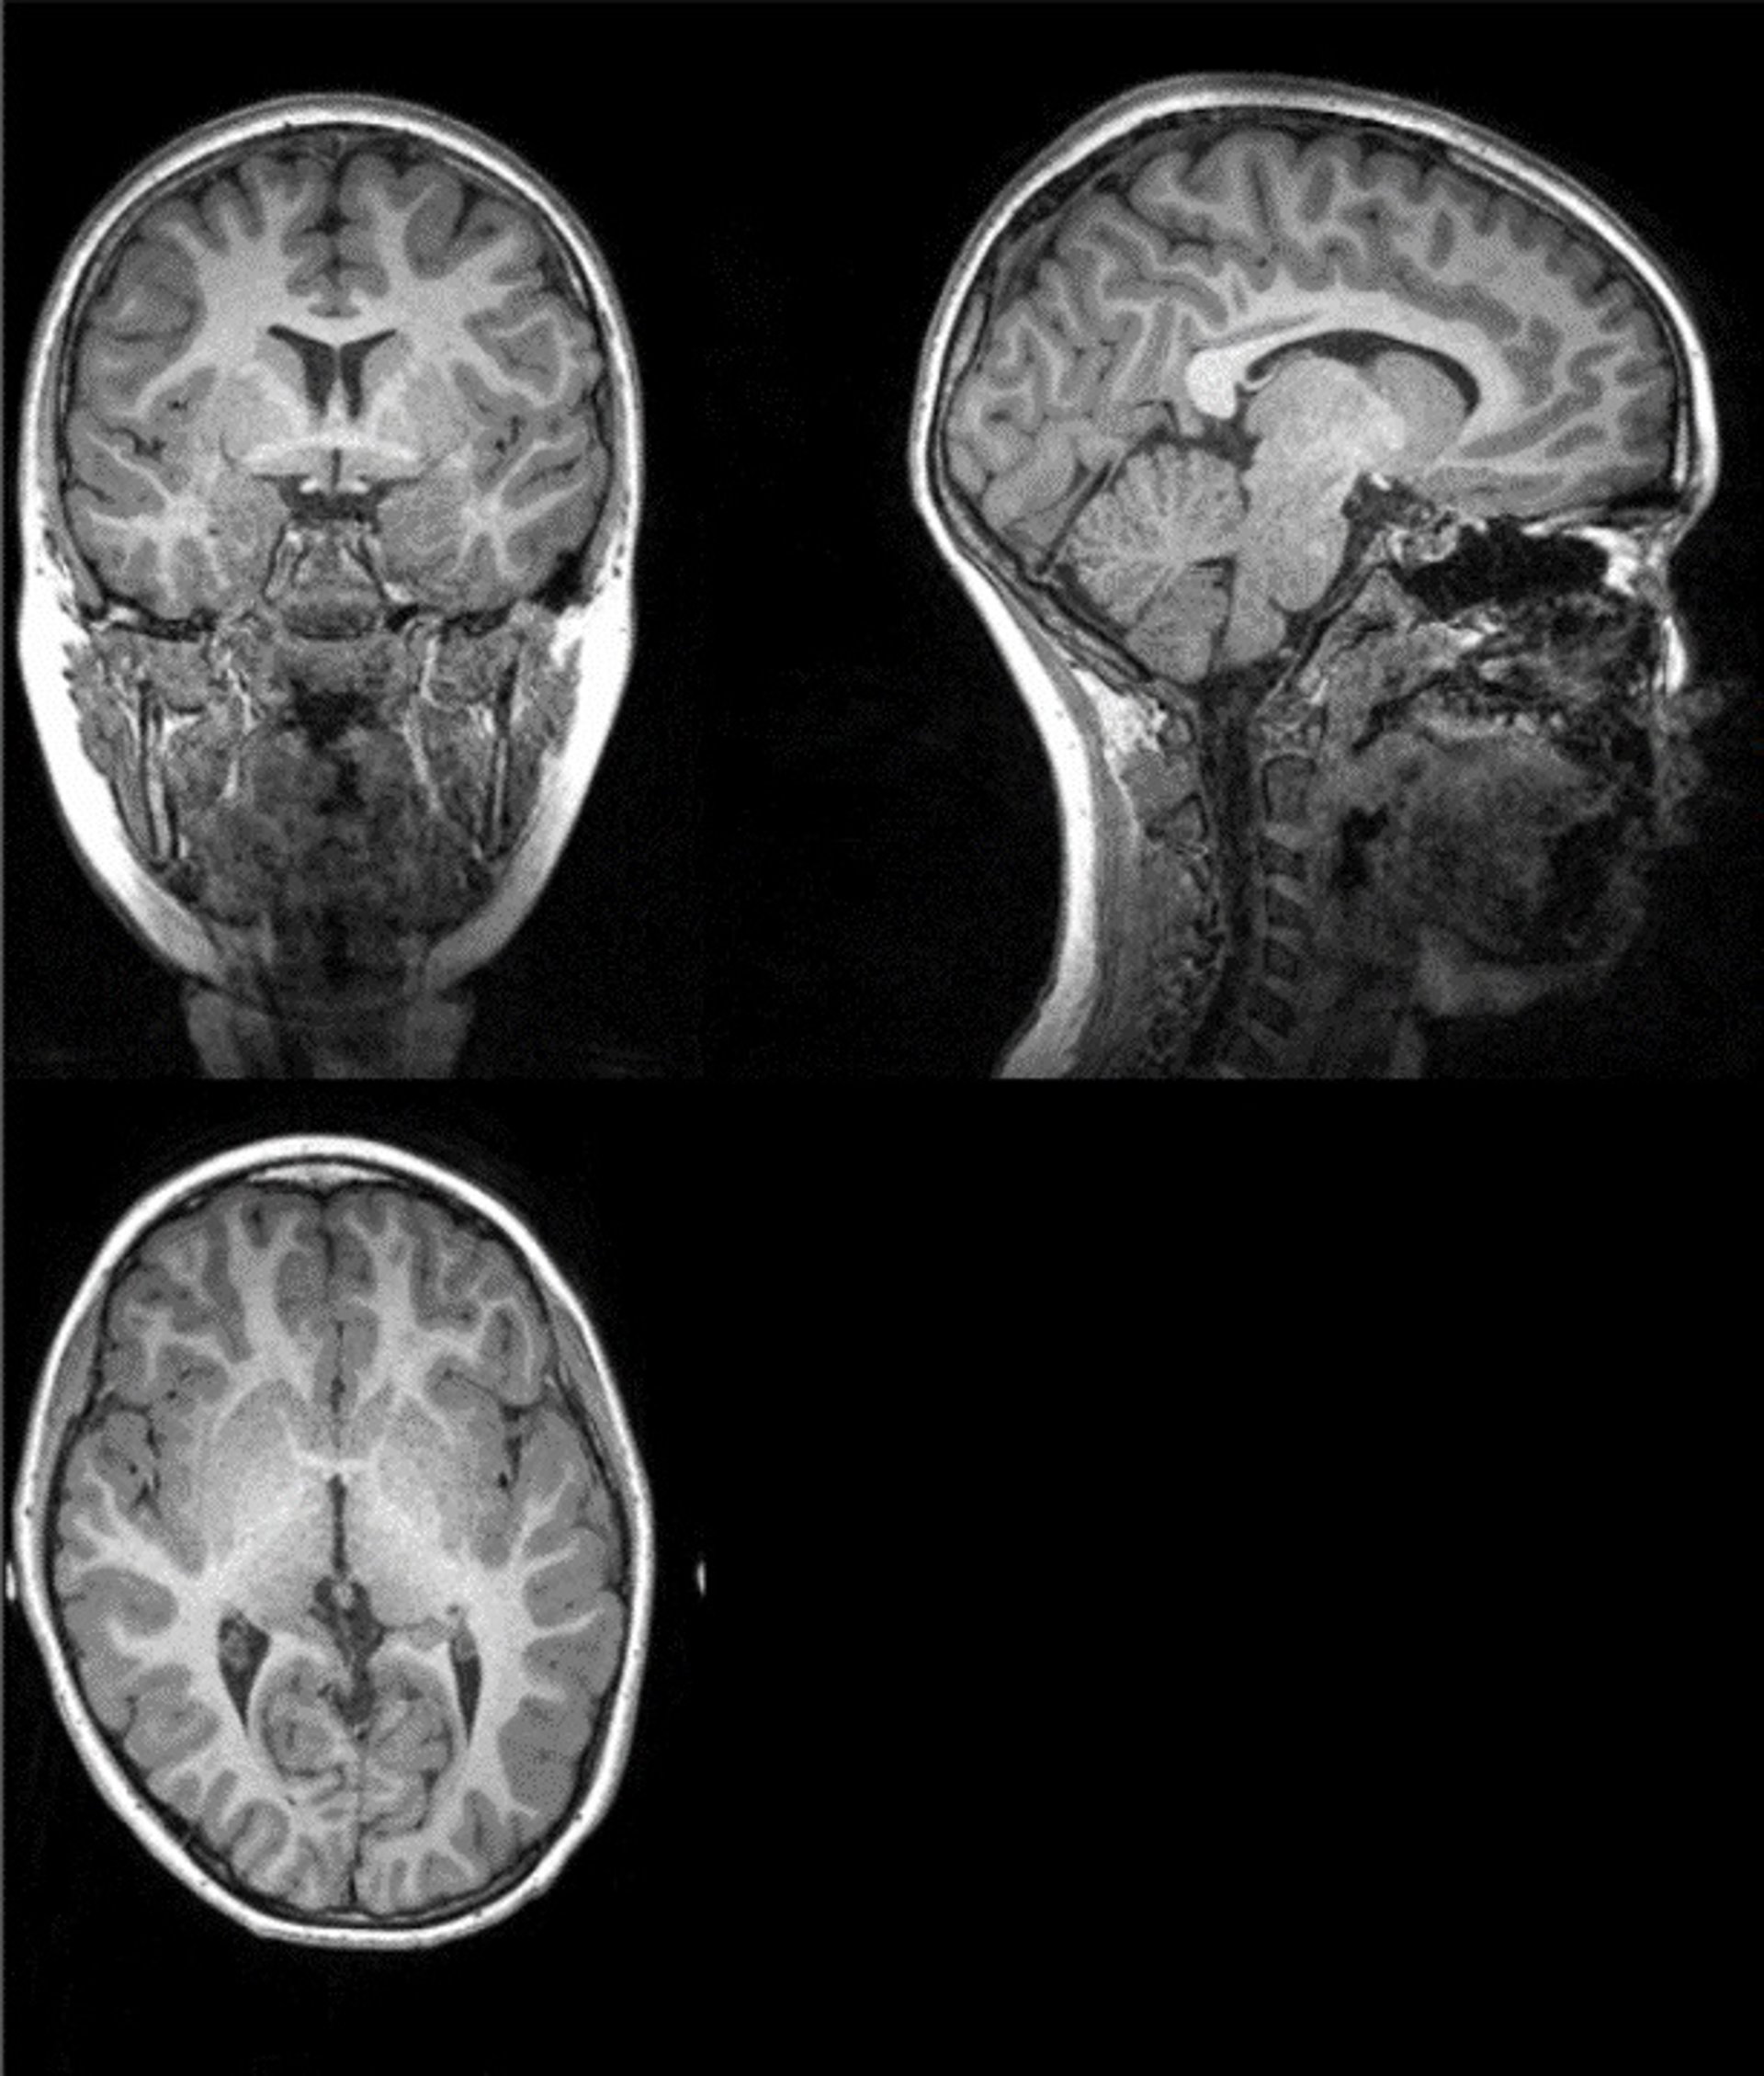

Ejemplo de imagen original de la resonancia magnética a partir de la cual investigadores de la UGR han extraído la cantidad total de materia gris, materia blanca, y cantidad total cerebral

Ejemplo de imagen original de la resonancia magnética a partir de la cual investigadores de la UGR han extraído la cantidad total de materia gris, materia blanca, y cantidad total cerebral - UGR